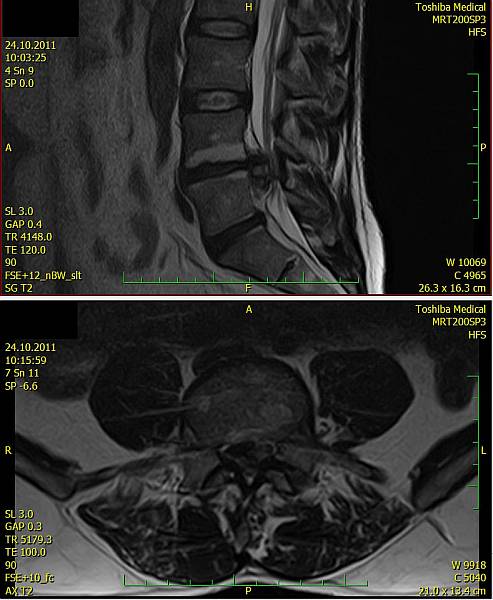

1. Žena, 48 let. Na MR patrná 8mm velká paramediální hernie L5/S1 vlevo s extruzí materiálu ploténky do epidurálního prostoru a útlakem kořenů L5 a S1 vlevo. Pacientce byla doporučena operace, kterou odmítla a zvolila alternativní postup s aplikací ozonu. Viz obr. 6a

Na kontrolním MR po 1 měsíci (po 2 aplikacích ozonu) periradikulárně je viditelné vymizení fragmentů v epidurálním prostoru a částečná retrakce meziobratlové ploténky. Subjektivně výrazná úleva, po 4 týdnech návrat do práce. Viz obr. 6b